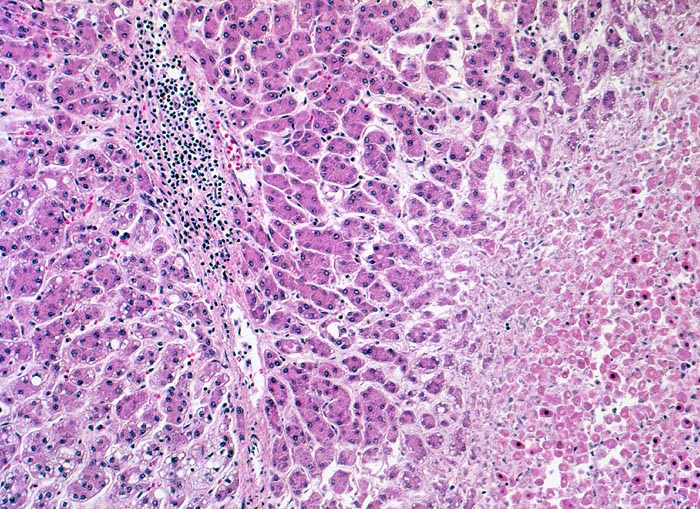

Morphologie: Makroskopisch imponiert das hepatozelluläre Karzinom als solitäre grosse Tumormasse, als zahlreiche zirrhoseartige Knoten oder als scharf begrenzter Knoten mit oder ohne Kapsel. Die tumorfreie Leber ist in der Mehrheit der Fälle zirrhotisch umgebaut. Mikroskopisch bilden die Tumorzellen mehr als 2 Zellen breite Trabekel ( 1237), kompakte Tumormassen ( 1229) oder pseudoglanduläre Strukturen (dilatierte Canaliculi) ( 1212)( 1199). Desmoplastisches Bindegewebe fehlt meist. Innerhalb des Tumors fehlen Portalfelder. Es finden sich lediglich Arterien. Etwa bei der Hälfte der Karzinome lässt sich intrazytoplasmatische oder intracanaliculäre Galle ( 1238) nachweisen. Immunhistochemisch lassen sich mit einem polyklonalen Antikörper gegen Carcinoembryonales Antigen (CEA) Gallecanaliculi zwischen den Tumorzellen nachweisen. Die Tumorzellen bilden keinen Schleim.

Innerhalb des Tumors Blutgefässe, aber keine Portalfelder.

Die Tumorzellen bilden Trabekel, welche überwiegend mehr als 2 Zellen breit sind und Pseudodrüsen.

Sinusoidartige Blutgefässe mit Endothelauskleidung verlaufen zwischen den Trabekeln und den Pseudodrüsen.

Tumorfreies Parenchym mit chronischer viraler Hepatitis (B und D): dichtes chronisches Entzündungsinfiltrat in den Portalfeldern übergreifend auf das Parenchym (Interfacehepatitis). Spärliche intralobuläre Entzündung mit Einzelzellnekrosen (Apoptosen). Fibrose der Portalfelder mit Septenbildung und unvollständigem zirrhotischem Umbau. Geringe gemischttropfige Verfettung des Leberparenchyms.